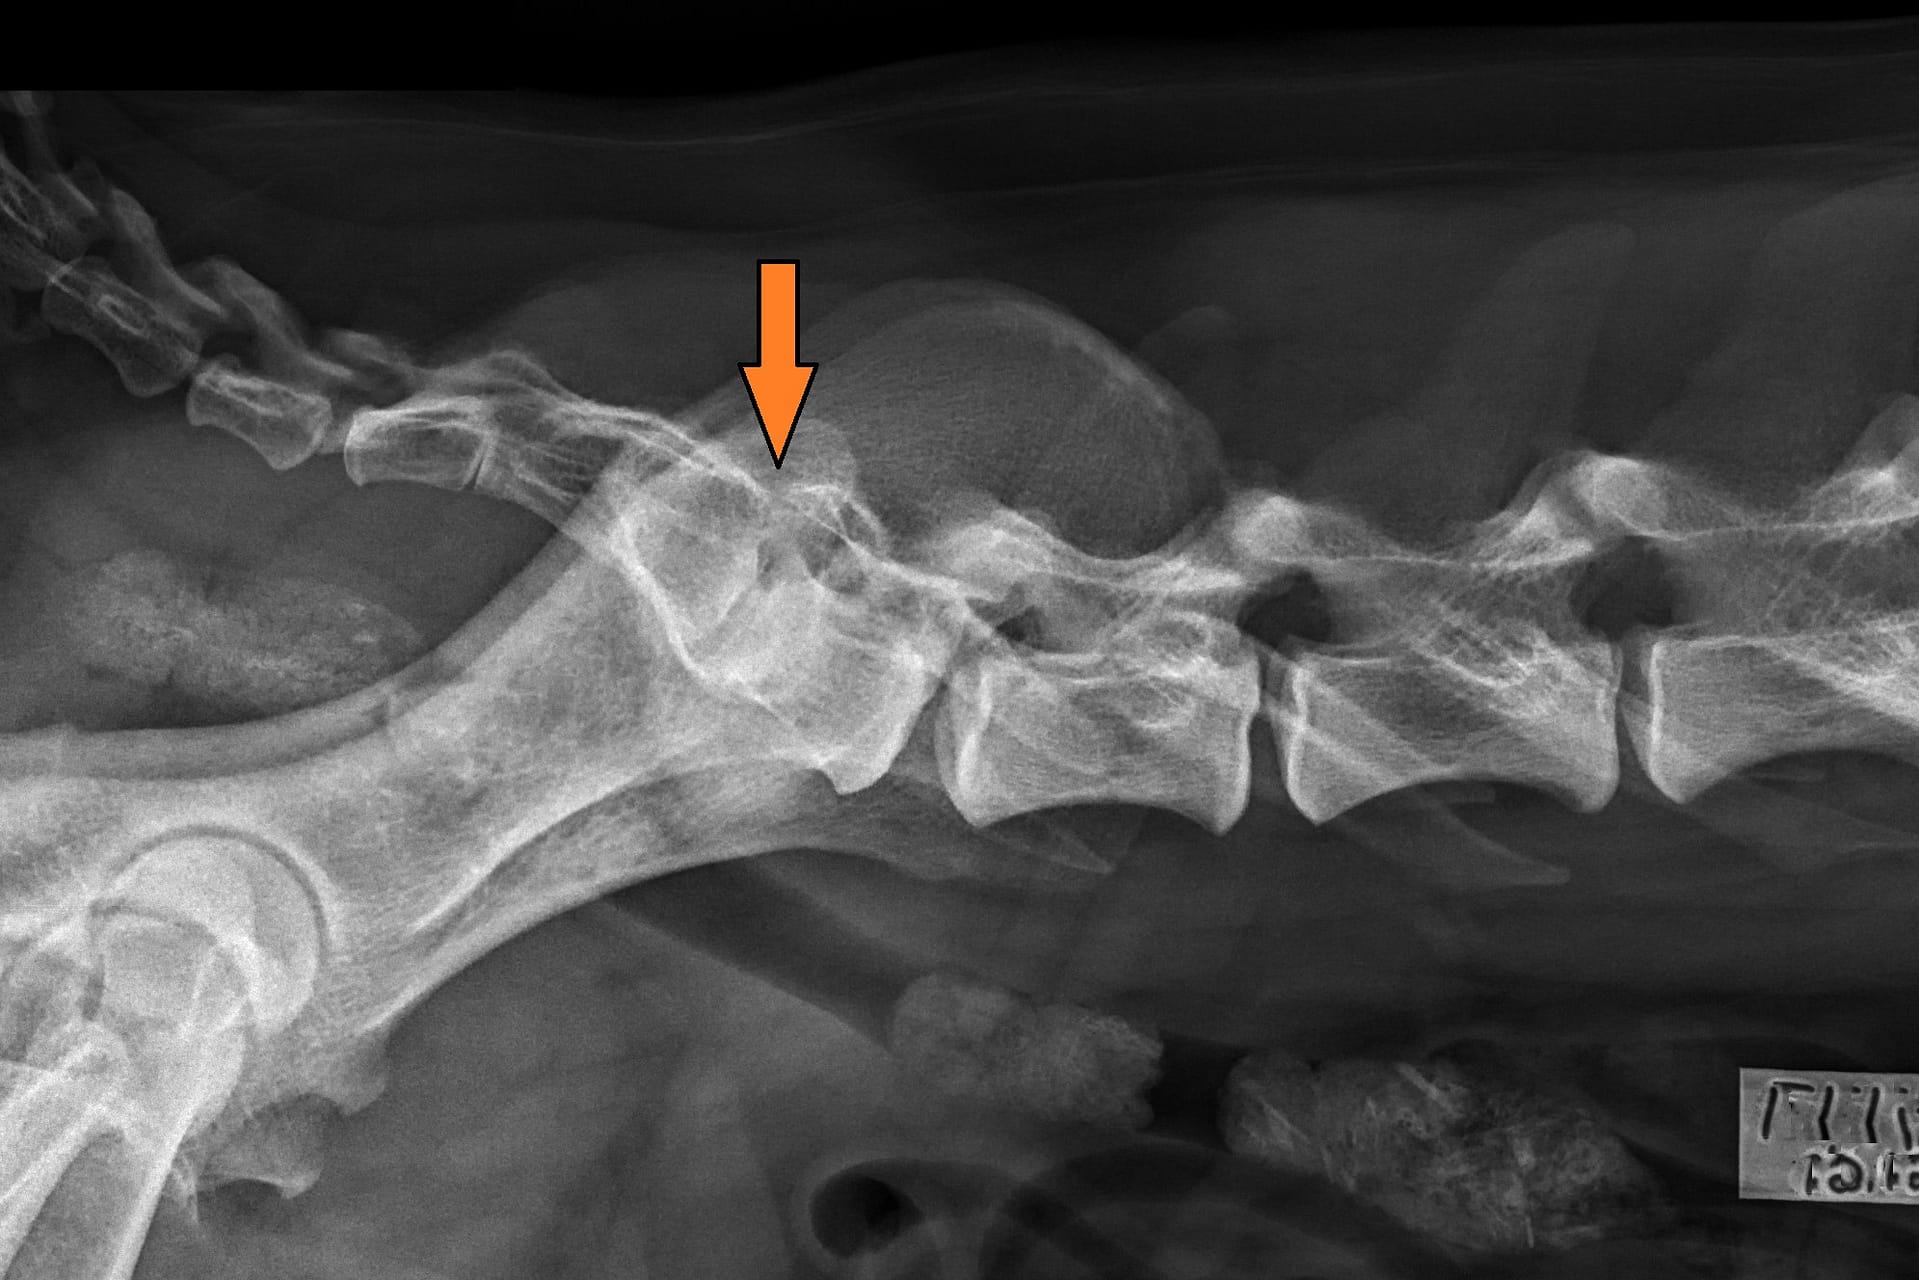

SPONDYLOOSI

Rhodesiankoirilla esiintyy myös spondyloosia, joka on selkärangan rappeumasairaus. Jonkinasteisen LTV:n omaavat rhodesiankoirat näyttävät olevan alttiimpia spondyloosille kuin spondyloosivapaat yksilöt. 253 selkäkuvatuista rhodesiankoirista 25 (9,9 %) on myös spondyloosi (joulukuu 2019). 7/253 ei ole lainkaan spondyloosilausuntoa useimpien ollessa liian nuoria spondyloosilausunnon saadakseen. Verrattuna normaalin lanne-ristinikaman omaaviin yksilöihin LTV1-LTV4-lausunnon saaneilla koirilla näyttää olevan kaksinkertainen riski spondyloosiin. Kuitenkin 25 koiran joukko on vielä liian pieni johtopäätösten tekemiseen. Selkäkipuisen koiran kohdalla voi olla haastavaa erotella LTV-muutoksesta ja spondyloosista aiheutuvaa kipua. .